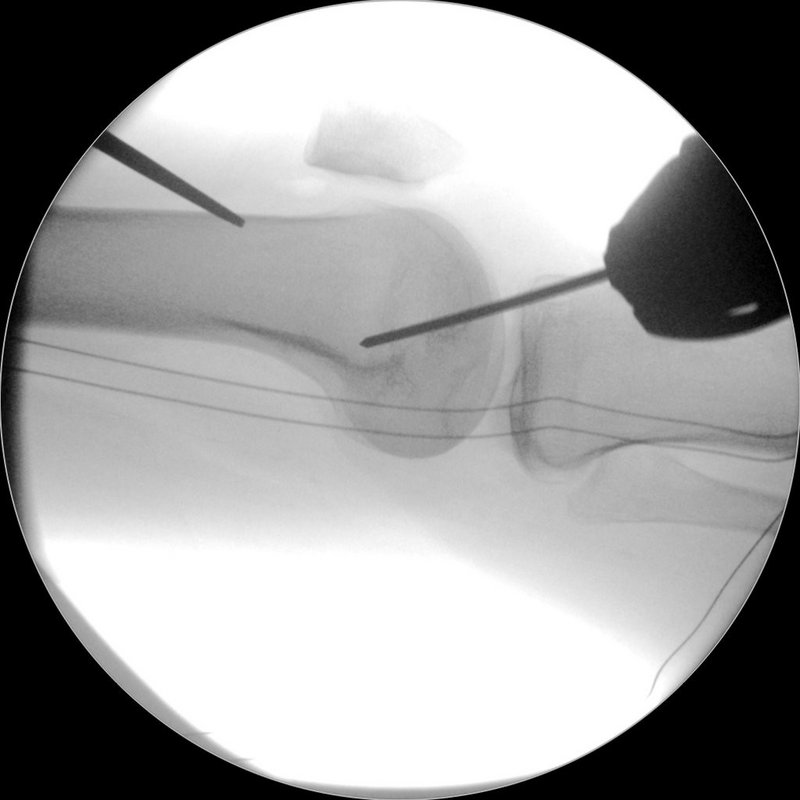

Meniskus

Der Meniskus fungiert als „Stoßdämpfer“ zwischen Oberschenkel und Unterschenkel, verbessert die Kongruenz der Gelenkpartner und trägt zusätzlich zur Stabilität des Kniegelenkes bei. Je nach Rissform, Patientenalter, traumatischer oder degenerativer Ursache bestehen unterschiedliche Behandlungsoptionen von konservativer Therapie bis hin zur operativen Versorgung mittels Teilresektion oder Meniskusnaht. Bei speziellen Meniskusverletzungen (z.B. der sogenannten Wurzel-Läsion) kann – um den Einheilungsprozess zu gewährleisten – auch ein Zusatzeingriff wie eine Umstellungsosteotomie bei O-Beinen nötig werden.

Bei jungen Patienten mit Meniskusverlust besteht auch die Möglichkeit einer sog. Meniskustransplantation, um langfristig das Fortschreiten der Arthrose hinauszuzögern. Hierbei wird aus einer Spenderbank ein bzgl. Größe und Form passender Spendermeniskus ausgewählt und nach Entfernung des defekten Eigenmeniskus im Gelenk fixiert.